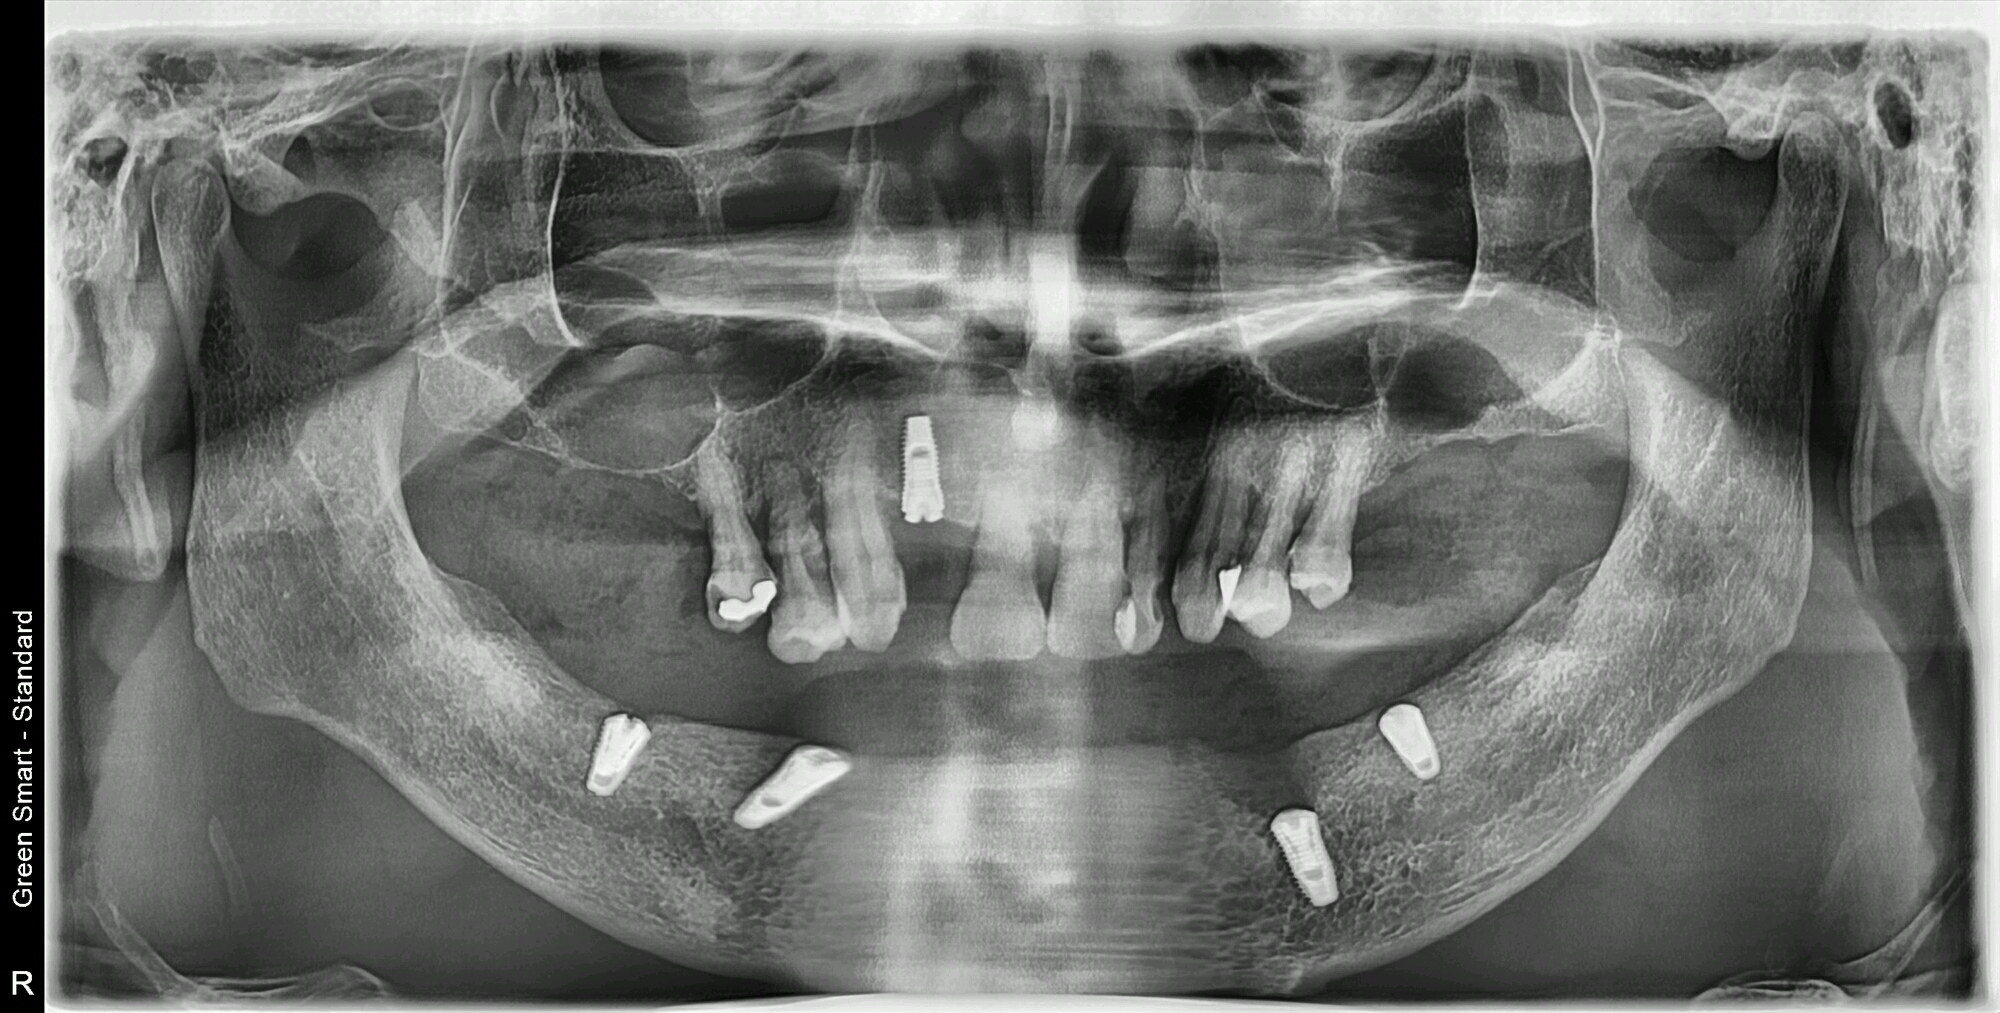

維港歡樂牙科謝醫生介紹:可以選擇all-on-4 植牙修復,同時,謝醫生分享咗一例All on 4的植牙個案。湯先生下排牙齒缺失,進行all on 4 一期植牙,上排種植一顆,當天完成一期手術植體植入,待三個月後進行二期植牙修復。

採用植體:南韓登騰種植體

植牙方式:All-on-4

All-on-4 總收費:52000元